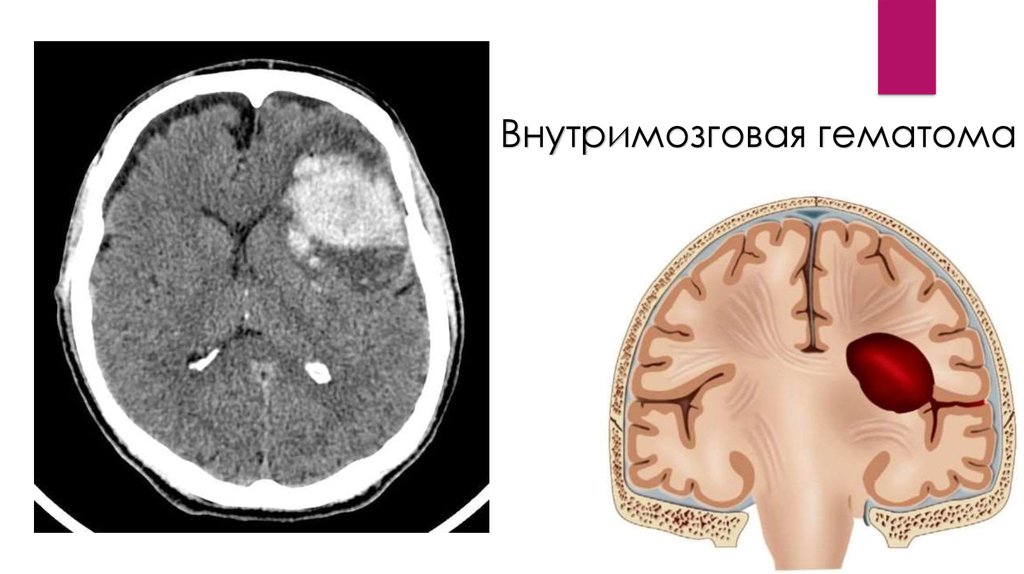

Внутримозговая гематома

внутримозговые